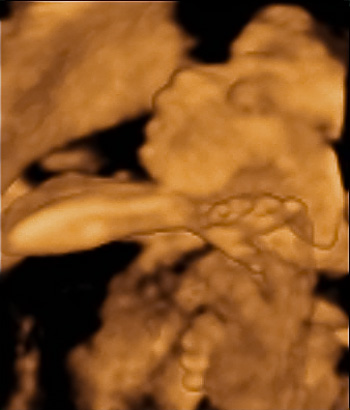

Az utolsó képen az ujjacskái láthatók.